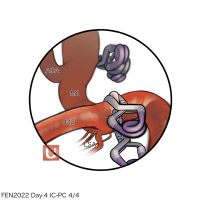

FEN2022シリーズ